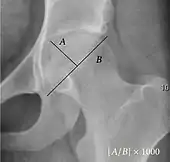

The most useful lines and angles that can be drawn in the pediatric pelvis assessing hip dysplasia are as follows:[3]

- (A) Hilgenreiner line, connects the inferior tips of the iliac bones,[4] at the triradiate cartilage. This line is used to measure the acetabular angle and as a reference for Perkin line.

- (B) Perkin line is perpendicular to Hilgenreiner line, touching the lateral margin of the acetabular roof.[5] This leads to four quadrants and a normal femoral head has to be located in the inferomedial quadrant. We can measure the lateral displacement of the femoral head with regard to the Perkin line by dividing the width of the head that crosses the Perkin line by the diameter of the head. The value for patients under 3 years must be 0 and in older children this ranges from 0 to 22%.

- (C) Shenton line is a continuous arc drawn from the inner edge of the femoral neck to the superior margin of the obturator foramen. In children over about 3 to 4 years of age, this line should be smooth and undisrupted, otherwise it may indicate a fracture or hip dysplasia.[6] However, in infants this line can be unreliable as it depends on the rotation of the hip when the image is taken.[7]

- (D) The acetabular index measures the acetabular roof slope. It is the most useful measure of acetabular dysplasia until 6 years of age. It is formed between Hilgenreiner line and the acetabular roof. In newborns, values of in males and in females are considered normal. It normally decreases with age:

- (E) The medial articular joint space is measured between the medial border of the femoral head or neck (when epiphysis is not ossified) and the acetabular platform. Normal values range between 5 and 12 mm. Differences greater than 1.5 mm between the two sides are considered abnormal.

- Reimer's migration index (MI), also called the femoral extrusion index,[3] is calculated if hip dysplasia is detected. It can be used to indicate hip dislocation. It is the horizontal distance (parallel to the Hilgenreiner Line) between the Perkin line and the lateral border of the ossification center of the femoral head, divided by the horizontal width of the ossification center. The migration index is normally less than 33% by most sources,[9] but 25% and 30% has also been suggested.[10]